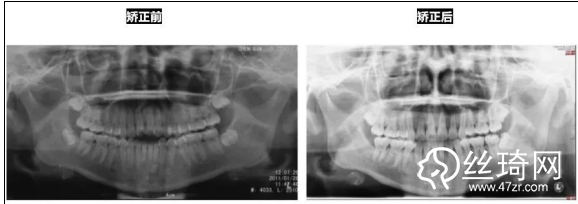

* 影像學檢查分析(以及調(diào)節(jié)前后影像對比):

全景片:

前后頭影測量結(jié)果對比: